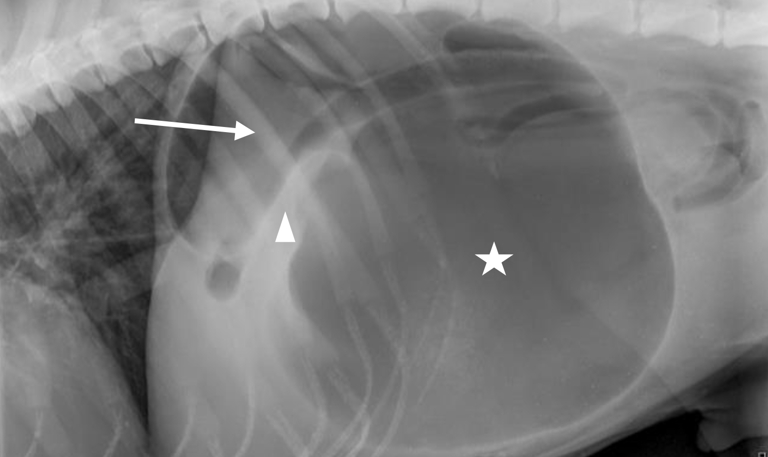

Case 2 - Captain (Case report)

Gastric dilatation and volvulus with partial splenectomy – German Shepherd Dog, 7y, male neutered